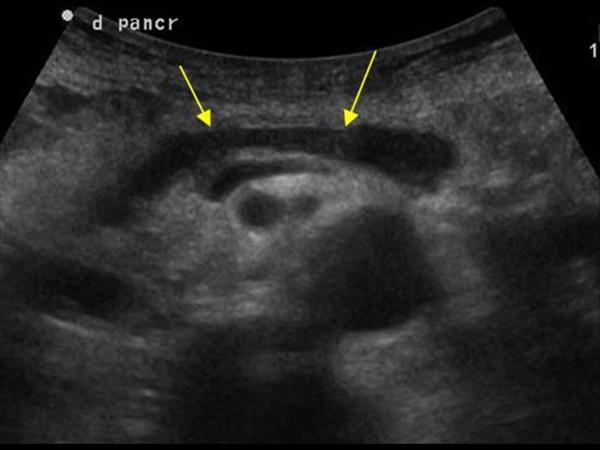

УЗИ диагностика кольцевидной поджелудочной железы: что важно знать